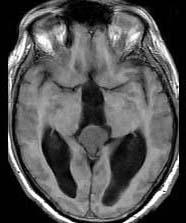

问题 15岁,男,头痛、呕吐,步态不稳,眼球震颤,性发育异常,MRI检查如图,最可能的诊断()

选项 A.松果体钙化 B.松果体瘤 C.脑膜瘤 D.生殖细胞瘤 E.畸胎瘤

答案 B